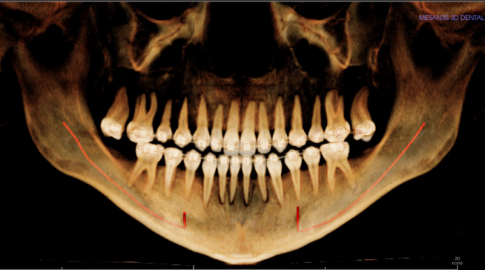

Diagnose:

Maxilläre Retrognathie, OK-Schmalkiefer, Hyperdivergenz, erschwerter Lippenschluss

Therapie:

Surgery First: Bignathe Umstellungsosteotomie (Minimalinvasive Le Fort I Osteotomie mit Vorverlagerung und simultaner Oberkieferdistraktion, gesonderte Spina Nasalis Osteotomie zur besseren Kontrolle von Oberlippenposition und -volumen, Anhebung der Nasenspitze, Unterkiefersegmentosteotomie 32-42 zur Vergrößerung der sagittalen Stufe (Dekompensation),

Kinnosteotomie, Side Wing Osteotomie mit Beckenkamminterponat)